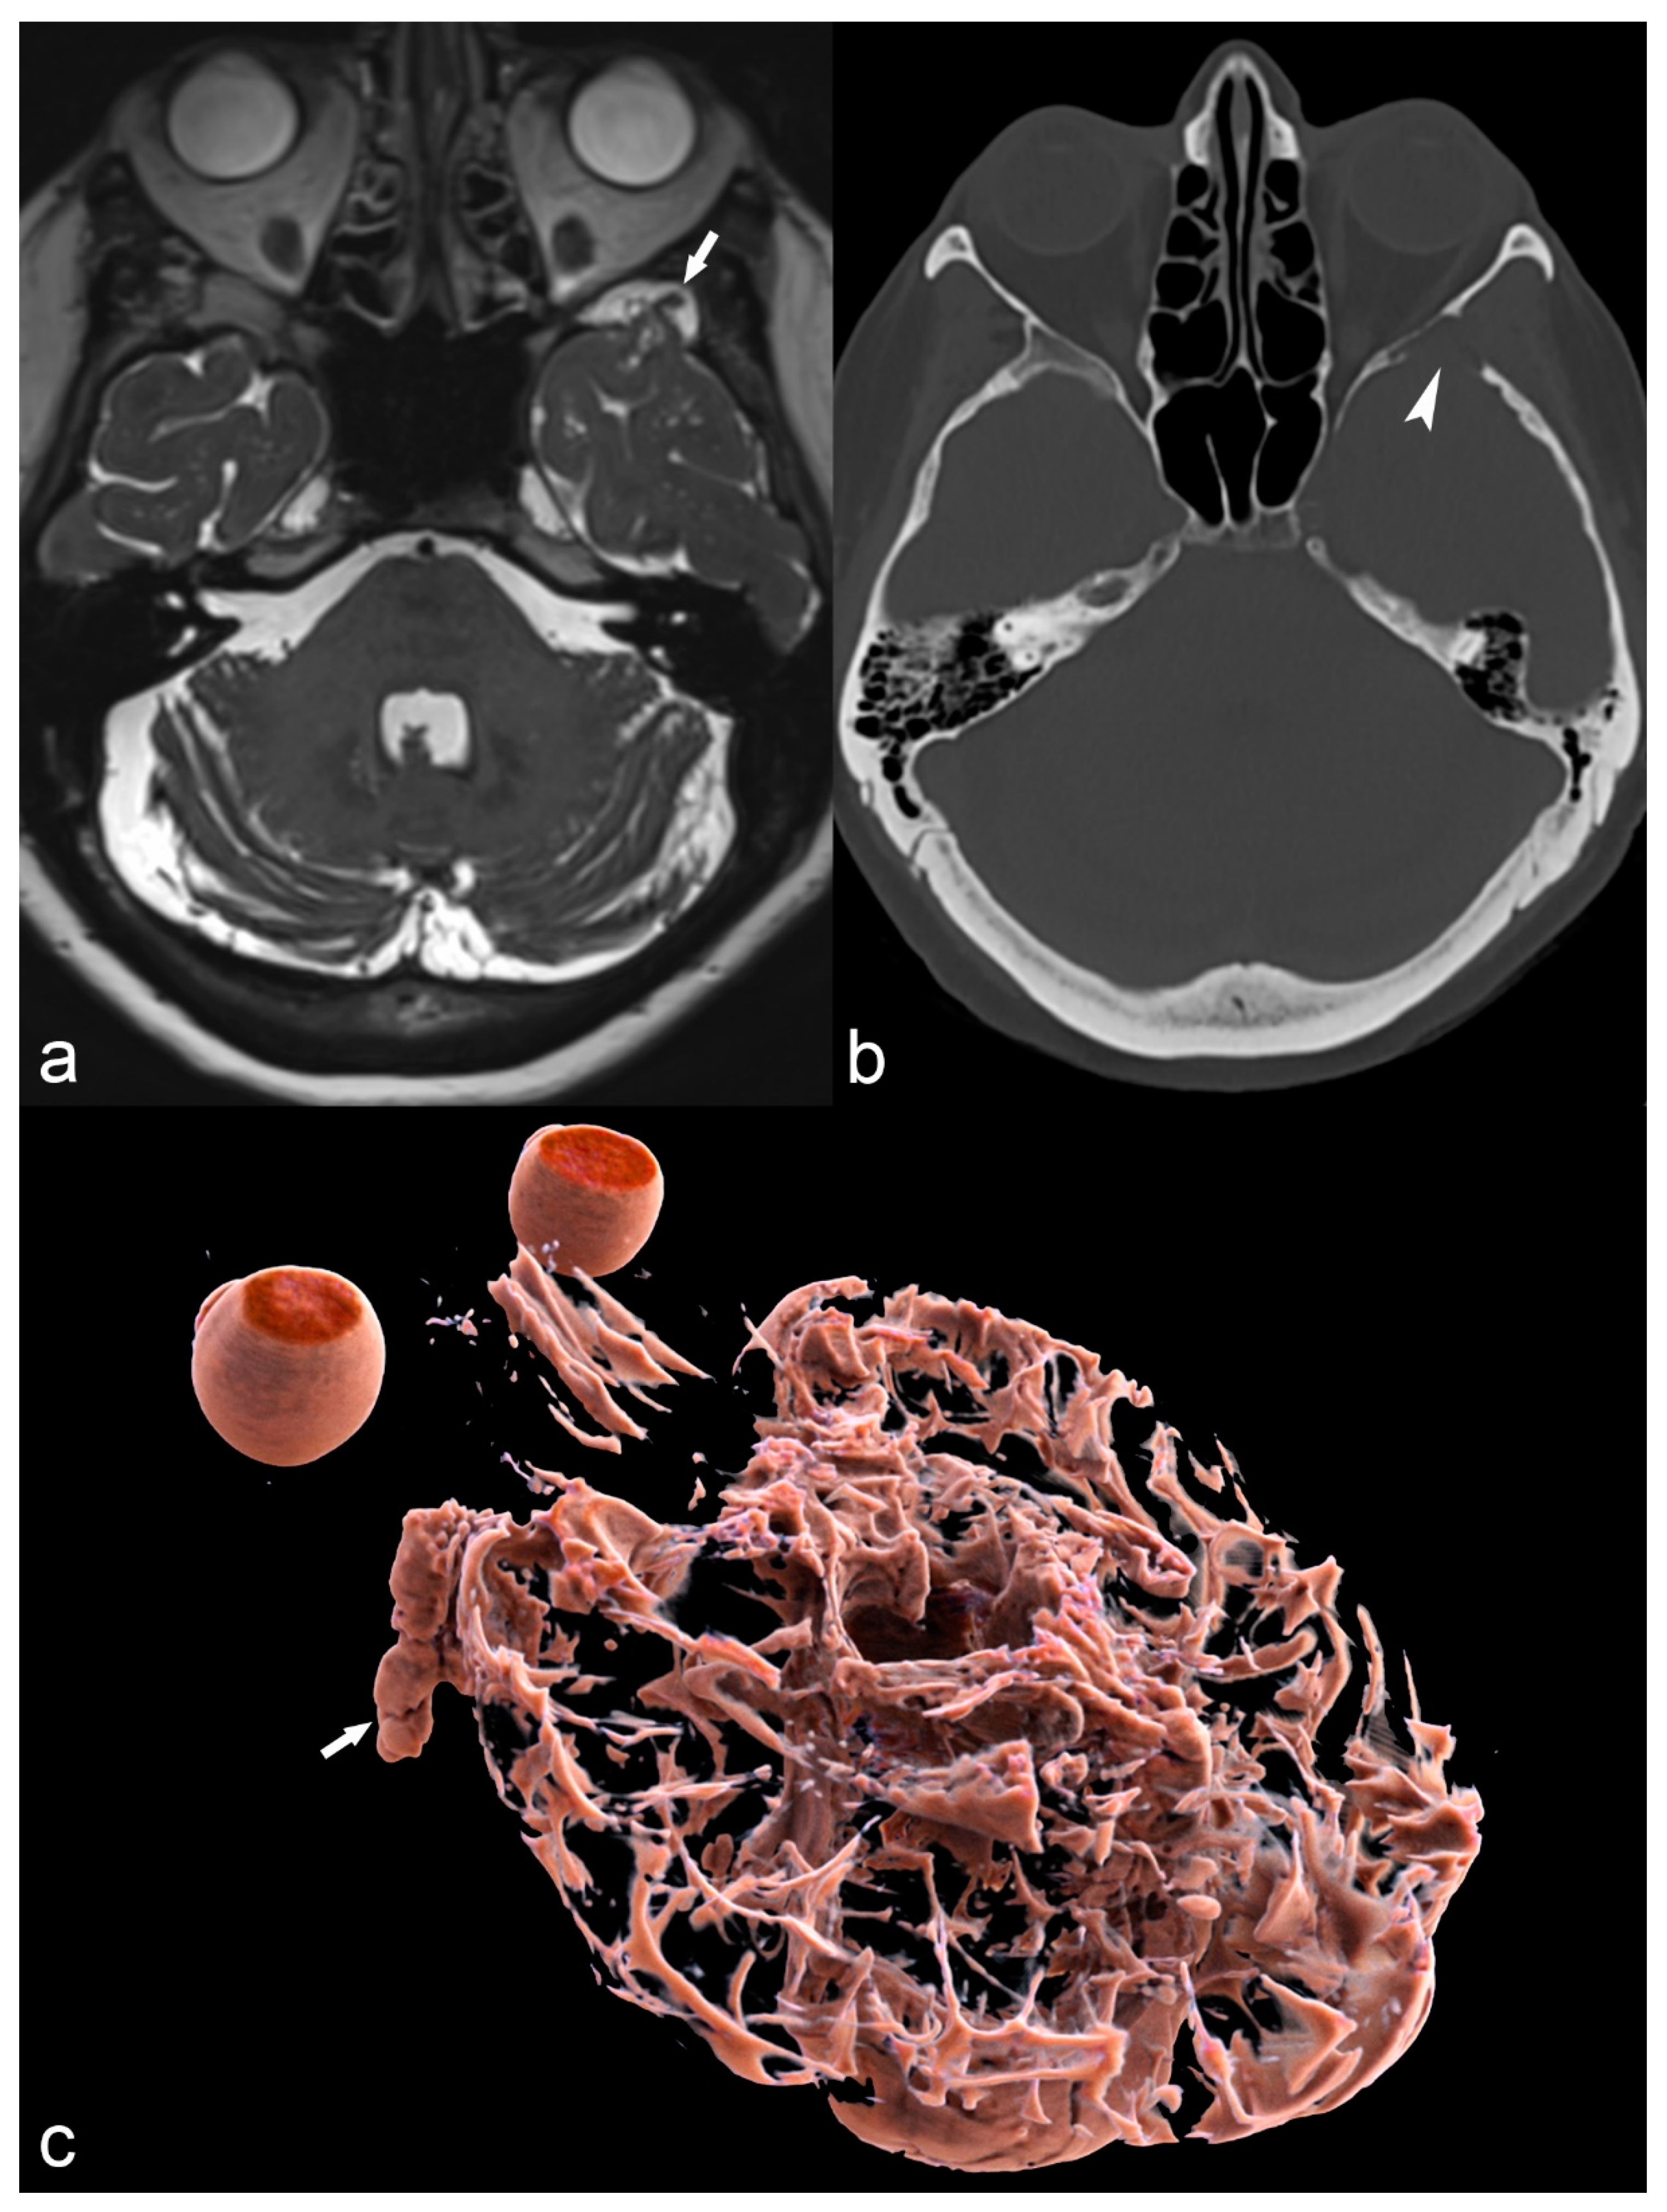

Figure 14.

68-year-old woman with left temporal meningoencephalocele. Axial 3D high-ponderated T2 sequence (a) shows herniation of abnormal brain parenchyma, meninges and cerebrospinal fluid (arrow) into a defect of the greater wing of the sphenoid bone, best seen on CT in the bone window (arrowhead in (b)). This is further illustrated by a 3D cinematic rendering of the 3D T2 acquisition with a left posterior-anterior oblique vantage point (c), which demonstrates the full caudal extent of the meningoencephalocele within the sphenoid bone (arrow).